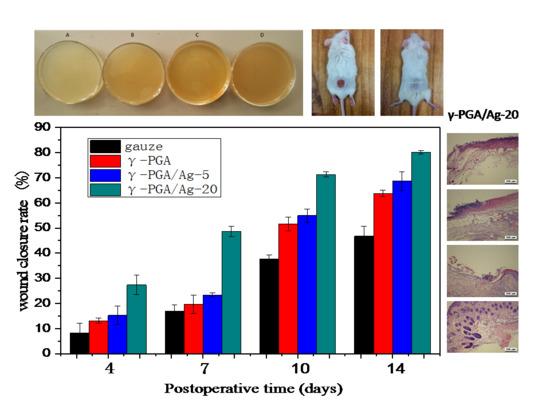

3.4. In Vivo Study

3.5. Histological Analysis

| A | B | Day 0 | Day 4 | Day 7 | Day 10 | Day 14 |

|---|---|---|---|---|---|---|

| gauze |  |  |  |  |  |

| γ-PGA |  |  |  |  |  | |

| ↓ | γ-PGA/Ag-5 |  |  |  |  |  |

| ||||||

| γ-PGA/Ag-20 |  |  |  |  |  |

| Wound Dressing | Day 4 | Day 7 | Day 10 | Day 14 |

|---|---|---|---|---|

| gauze |  |  |  |  |

| γ-PGA |  |  |  |  |

| γ-PGA/Ag-5 |  |  |  |  |

| γ-PGA/Ag-20 |  |  |  |  |

| Positivecontrol |  |  |  |  |